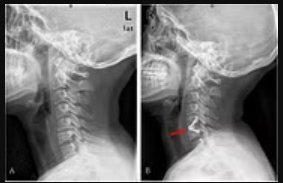

Few diseases are as disruptive and persistent as chronic neck pain, which can cast a long shadow over every aspect of daily life, from working to sleeping. When conservative treatments like physical therapy, medication, and injections fail to provide lasting relief, and the pain intensifies, radiates into the arms, or causes debilitating numbness and weakness, the conversation often turns to a more definitive intervention: Neck Surgery Edison. Far from a simple decision, this intricate field encompasses a range of delicate procedures designed to alleviate nerve compression, stabilize the cervical spine, repair damaged discs, and ultimately restore function and quality of life for those whose very movement has become a source of agony.